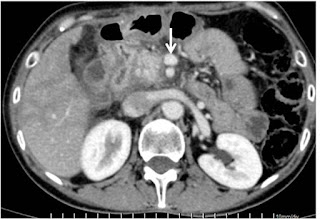

In July 2019, almost 11 months after her initial double bypass surgery and having completed CRT, Ms A again reported to our clinic. She appeared in good health and was therefore re-evaluated. Her repeat pancreatic protocol CT scan and PET – CT scan showed that there was a remarkable reduction in the size of the tumor (Figure 2) and no spread to other organs of the body.

Figure 2. Post CRT Pancreatic protocol CT scan. SMA & SMV free of tumor